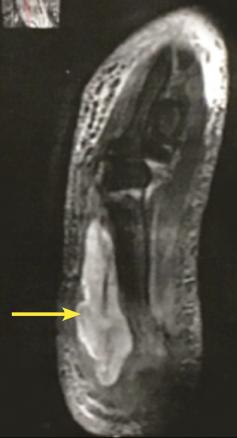

Cette femme de 60 ans, diabétique, consultait pour une tuméfaction hyperalgique du bras gauche depuis 15 jours. La patiente était fébrile. L’examen dermatologique notait une plaque nodulaire inflammatoire douloureuse de la face postérieure du bras (fig. 1 ), et une impotence fonctionnelle, sans porte d’entrée. Le bilan montrait une hyperglycémie à 2,6 g /L avec une hémoglobine glyquée à 15 % ; une hyperleucocytose à polynucléaires neutrophiles ; la protéine C-réactive, la créatine phosphokinase et les lacticodéshydorgénases étaient élevées. L’imagerie par résonance magnétique (IRM [fig. 2 ]) montrait une pyomyosite du muscle triceps avec une arthrite réactionnelle et une lame d’épanchement non ponctionnable. Une triple antibiothérapie et insulinothérapie étaient prescrites. Les symptômes persistant, un drainage chirurgical était fait (fig. 3 ). L’analyse du pus isolait un Staphylocoque aureus multisensible. Les suites post-opératoires étaient simples.

Peu de cas de pyomyosite avec arthrite réactionnelle sont rapportés. La pyomyosite est une infection bactérienne du muscle strié.1 Cette pathologie, fréquente dans les zones tropicales, est souvent causée par le Staphylocoque aureus ;2 elle est due à une bactériémie provenant d’une source souvent indéterminée.2 Les facteurs prédisposant sont le traumatisme et l’immunodépression. Le diagnostic peut être difficile ou retardé. Un examen clinique minutieux et une bonne palpation permettent de suspecter les collections profondes. L’IRM est l’examen clé, spécifique, qui permet de retenir le diagnostic dès la phase débutante en montrant3 un hypersignal T2 (fig. 2 ). Le traitement repose sur la gestion des facteurs de risque, l’antibiothérapie et le drainage.